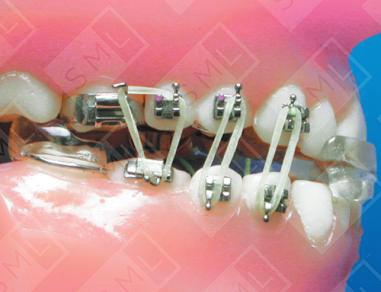

The lower is a wire-bodied appliance composed of an anterior bite block that covers the four lower anteriors and a pair of posterior bite blocks which cover the last molar on each side of the arch. Bonded hooks, buttons, or brackets are placed on the upper and lower cuspids, bicuspids, and first molars. When the lower appliance is in place, vertical elastics are used to initiate eruption of these teeth. By wearing this device a minimum of 12 hours a day (evenings and during sleep) eruption will occur much faster than it could through passive eruption alone.